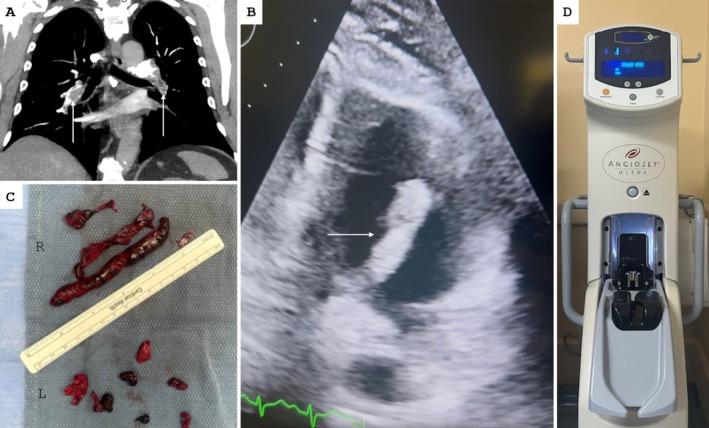

Percutaneous Thrombectomy Using AngioJet in Acute Pulmonary Embolism With Clot in Transit.

Percutaneous pulmonary thrombectomy using the AngioJet device is a feasible option for the management of acute pulmonary embolism with a clot in transit in selected high-risk patients. Further large-scale studies are needed to better establish the safety and efficacy of percutaneous thrombectomy for clot in transit in high-risk populations.